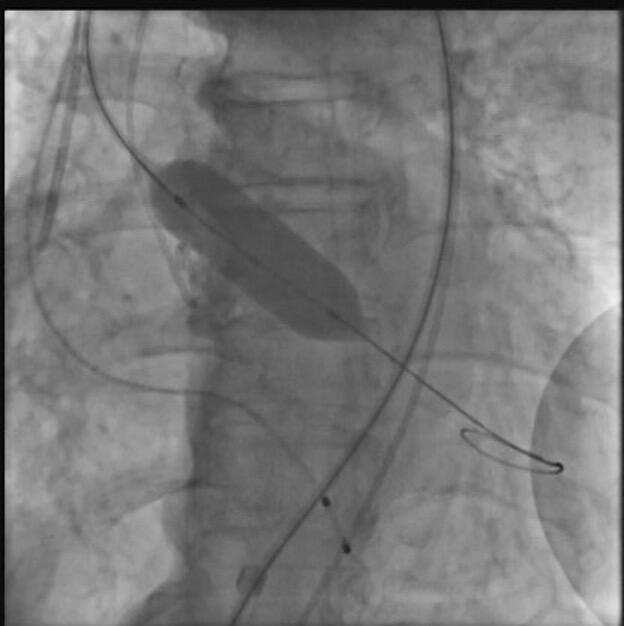

The patient was taken up for TAVR via a left common femoral artery (CFA) approach. The aortic valve was crossed (Figure 1A), and pre-dilatation was done using an 18-mm x 40-mm Mammoth balloon catheter (Meril Life Sciences) (Figure 1B). A 24.5-mm Myval transaortic valve (Meril Life Sciences) was introduced inside a Python expandable introducer sheath (Meril Life Sciences). However, the device could not be negotiated in the distal external iliac artery (EIA) due to calcium. The arrow in Figure 2A shows calcium in the distal EIA. The artery forceps depicts a marker for the distal end of the Python sheath. The sheath was withdrawn in the distal EIA; right CFA puncture was done and a 7F crossover sheath was placed. Intravascular lithotripsy (IVL) was done using a 7-mm x 60-mm IVL balloon; 30 pulses at 4 atm followed by 30 pulses at 6 atm were given (Figure 2B).

Following this, the sheath could be advanced proximally and the 24.5-mm Myval transaortic valve was negotiated and deployed (Figure 2C). A check angiogram showed good flow across the common iliac artery and EIA with no dissection (Figure 3). The puncture site was closed using a Perclose ProGlide Suture-Mediated Closure System (Abbott Cardiovascular). n